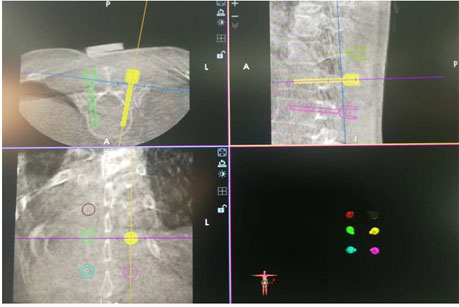

50岁的张先生,因摔伤致腰2椎体骨折到北京友谊医院平谷医院骨科就诊,完善术前各项检查,符合腰椎骨折机器人手术的指征。经过我院骨科团队术前病例讨论,为患者制定了“全麻下骨科机器人辅助腰椎骨折经皮复位椎弓根钉内固定术”的手术方案。手术过程中,骨科团队首先通过C型臂三维扫描手术部位,将数据导入机器人主机并进行手术路径规划,然后将机器人机器臂移动至目标椎体,机器臂按照规划路径定位至椎弓根钉进针点,安装套筒、打入克氏针,C型臂透视验证满意后旋入经皮椎弓根螺钉,所有操作一步到位。最后C型臂透视检查骨折复位,脊柱生理序列恢复满意,内固定物位置理想。

(天玑骨科机器人主机进行手术路径规划)